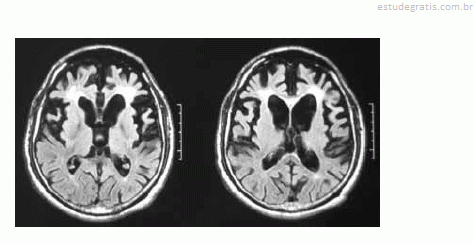

Uma mulher de 55 anos de idade, sem comorbidades, há três anos começou a apresentar distúrbio do comportamento, comprometimento do senso moral, da autocrítica, do poder de abstração e da memória. No exame, ela pouco colaborava com o examinador, possuía uma rigidez axial e apendicular, além de sutil tremor em repouso. O exame de imagem (RNM) a seguir foi realizado para auxiliar o diagnóstico.

Com base nesse quadro clínico, julgue os itens subsequentes.